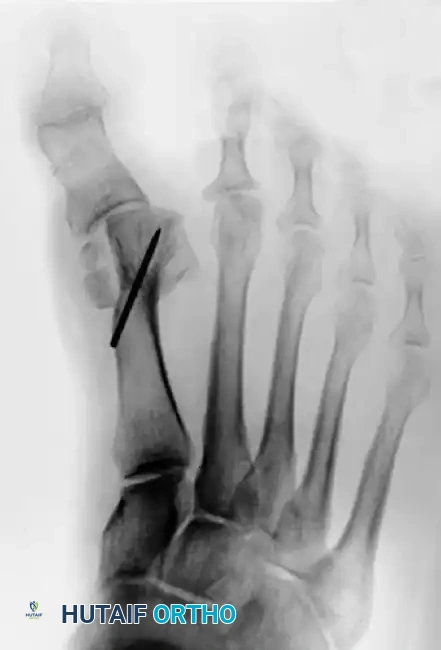

Figure 81-78: A passively correctable dynamic hallux varus deformity, demonstrating the multiplanar nature of the condition prior to becoming rigidly fixed.

Figure 81-79: (A) Preoperative hallux valgus deformity. (B) Postoperative dislocation of the tibial sesamoid following a distal metatarsal osteotomy combined with a fibular sesamoidectomy, leading to profound muscle imbalance.